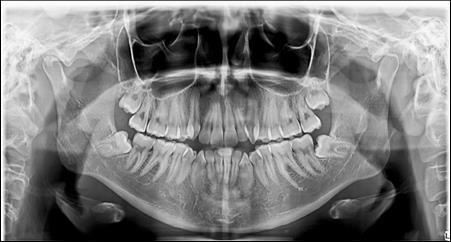

The panoramic radiograph showed bilateral mandibular third molars. The level of alveolar bone crest was within the normal range. (Figure 3)

Figure 3.Pretreatment panoramic X-ray